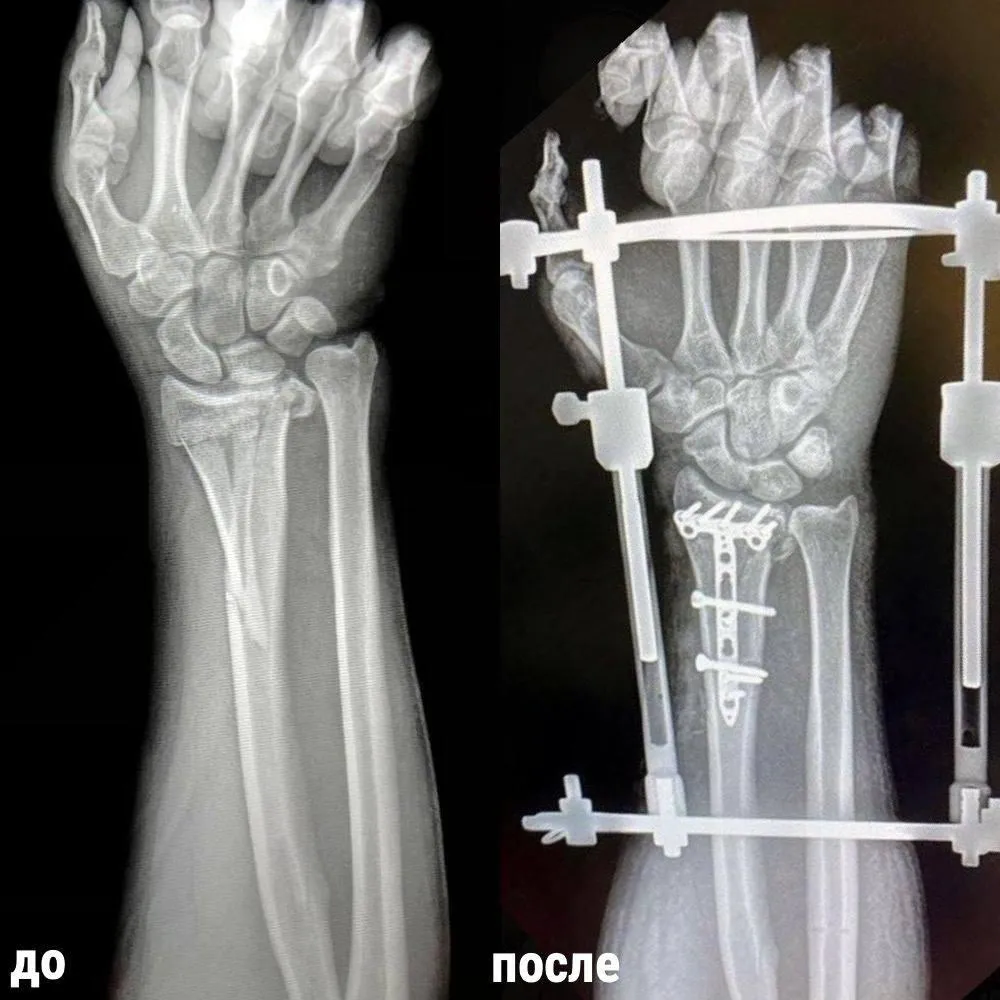

Спустя день пациенту поставили аппараты Илизарова на оба предплечья и соединили костные отломки правой лучевой кости специальной пластиной.

«При этом у пациента появилась возможность выполнять

минимально необходимый объем движений, чтобы самому себя обслуживать», – уточнил

Петр Лапынин.